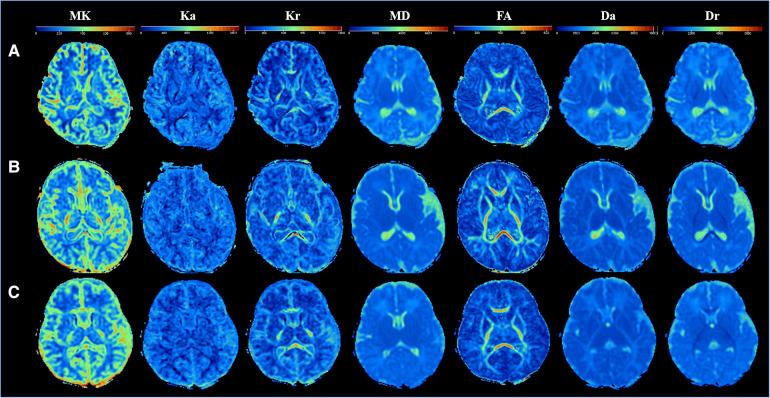

Application of diffusion kurtosis imaging in neonatal brain development.

Deviations from the regular pattern of growth and development could lead to early childhood diseases, suggesting the importance of evaluating early brain development. Through this study, we aimed to explore the changing patterns of white matter and gray matter during neonatal brain development using diffusion kurtosis imaging (DKI).

The mean kurtosis (MK), axial kurtosis (Ka), radial kurtosis (Kr), and fractional anisotropy (FA) values showed positive correlations, whereas mean diffusion (MD), axial diffusion (Da), and radial diffusion (Dr) values showed negative correlations with the age at the time of brain MRI acquisition. The absolute correlation coefficients between MK values of almost all ROIs (except genu of the corpus callosum and frontal white matter) and the age at the time of brain MRI acquisition were greater than other metrics. The kurtosis parameters and FA values of central white matter were significantly higher than that of peripheral white matter, whereas the MD and Dr values were significantly lower than that of peripheral white matter. The MK value of the posterior limb of the internal capsule was the highest among the white matter areas. The FA value of the splenium of the corpus callosum was significantly higher than that of the other white matter areas. The kurtosis parameters and FA values of globus pallidus and thalamus were significantly higher than those of the caudate nucleus and putamen, whereas the Da and Dr values of globus pallidus and thalamus were significantly lower than those of the caudate nucleus and putamen. The relative change rates of kurtosis parameters and FA values of all ROIs were greater than those of MD, Da, and Dr values. The amplitude of MK values of almost all ROIs (except for the genu of the corpus callosum and central white matter of the centrum semiovale level) was greater than that of other metrics. The relative change rates of the Kr values of most ROIs were greater than those of the Ka value, and the relative change rates of the Dr values of most ROIs were greater than those of the Da value.

DKI parameters showed potential advantages in detecting the changes in brain microstructure during neonatal brain development.